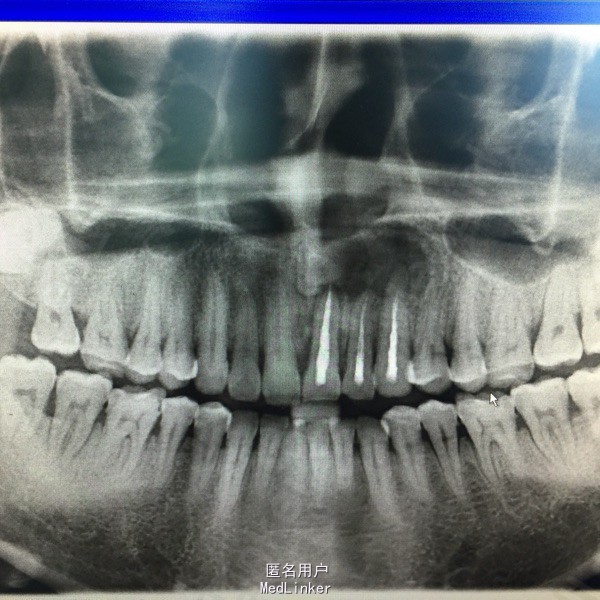

患者每日以生理盐水冲洗4次,每三个月复查。9个月后,复查全景牙片:囊肿消失,骨质形成,无需二次手术。